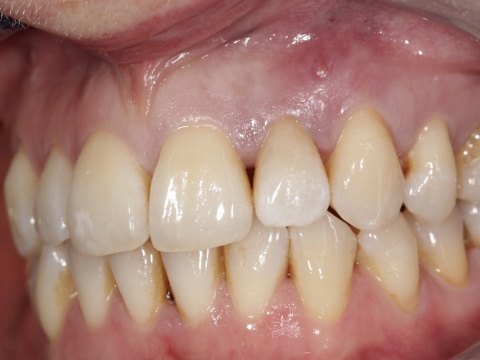

Eine 39-jährige Soldatin stellte sich im Januar 2020 mit Druckbeschwerden Regio 22 in unserer Abteilung vor. Wie auch in der vorangegangenen Falldarstellung konnten die Beschwerden mit Druck auf das Vestibulum verstärkt werden. Der Perkussionstest fiel deutlich positiv, der Vitalitätstest hingegen negativ aus. Eine erhöhte Lockerung des Zahnes lag, trotz des eindrucksvollen Röntgenbefundes, nicht vor. Erste Beschwerden traten laut Aussage der Patientin bereits 2014 auf. Das zu diesem Zeitpunkt angefertigte Röntgenbild zeigte keinen signifikanten pathologischen Befund, woraufhin die Situation weiterhin beobachtet wurde. Das aktuell angefertigte Röntgenbild zeigte eine umfangreiche periapikale Osteolyse, welche sich bis zu den Wurzelspitzen 21 und 23 erstreckte. Der Vitalitätstest der beiden benachbarten Zähne fiel positiv aus.

Bei der Kontrolle zwei Monate später war die Patientin vollkommen beschwerdefrei und die Fistelung ausgeheilt. Lediglich die Verfärbungen in Folge der unterstützenden chemischen Reinigung mit einem chlorhexidinhaltigen Präparat empfand die Patientin als ästhetisch störend.

die Fistelung Region 22 ist annähernd abgeklungen.

Zähne resultierten aus der Anwendung eines chlorhexidinhaltigenhaltigen

Präparates.